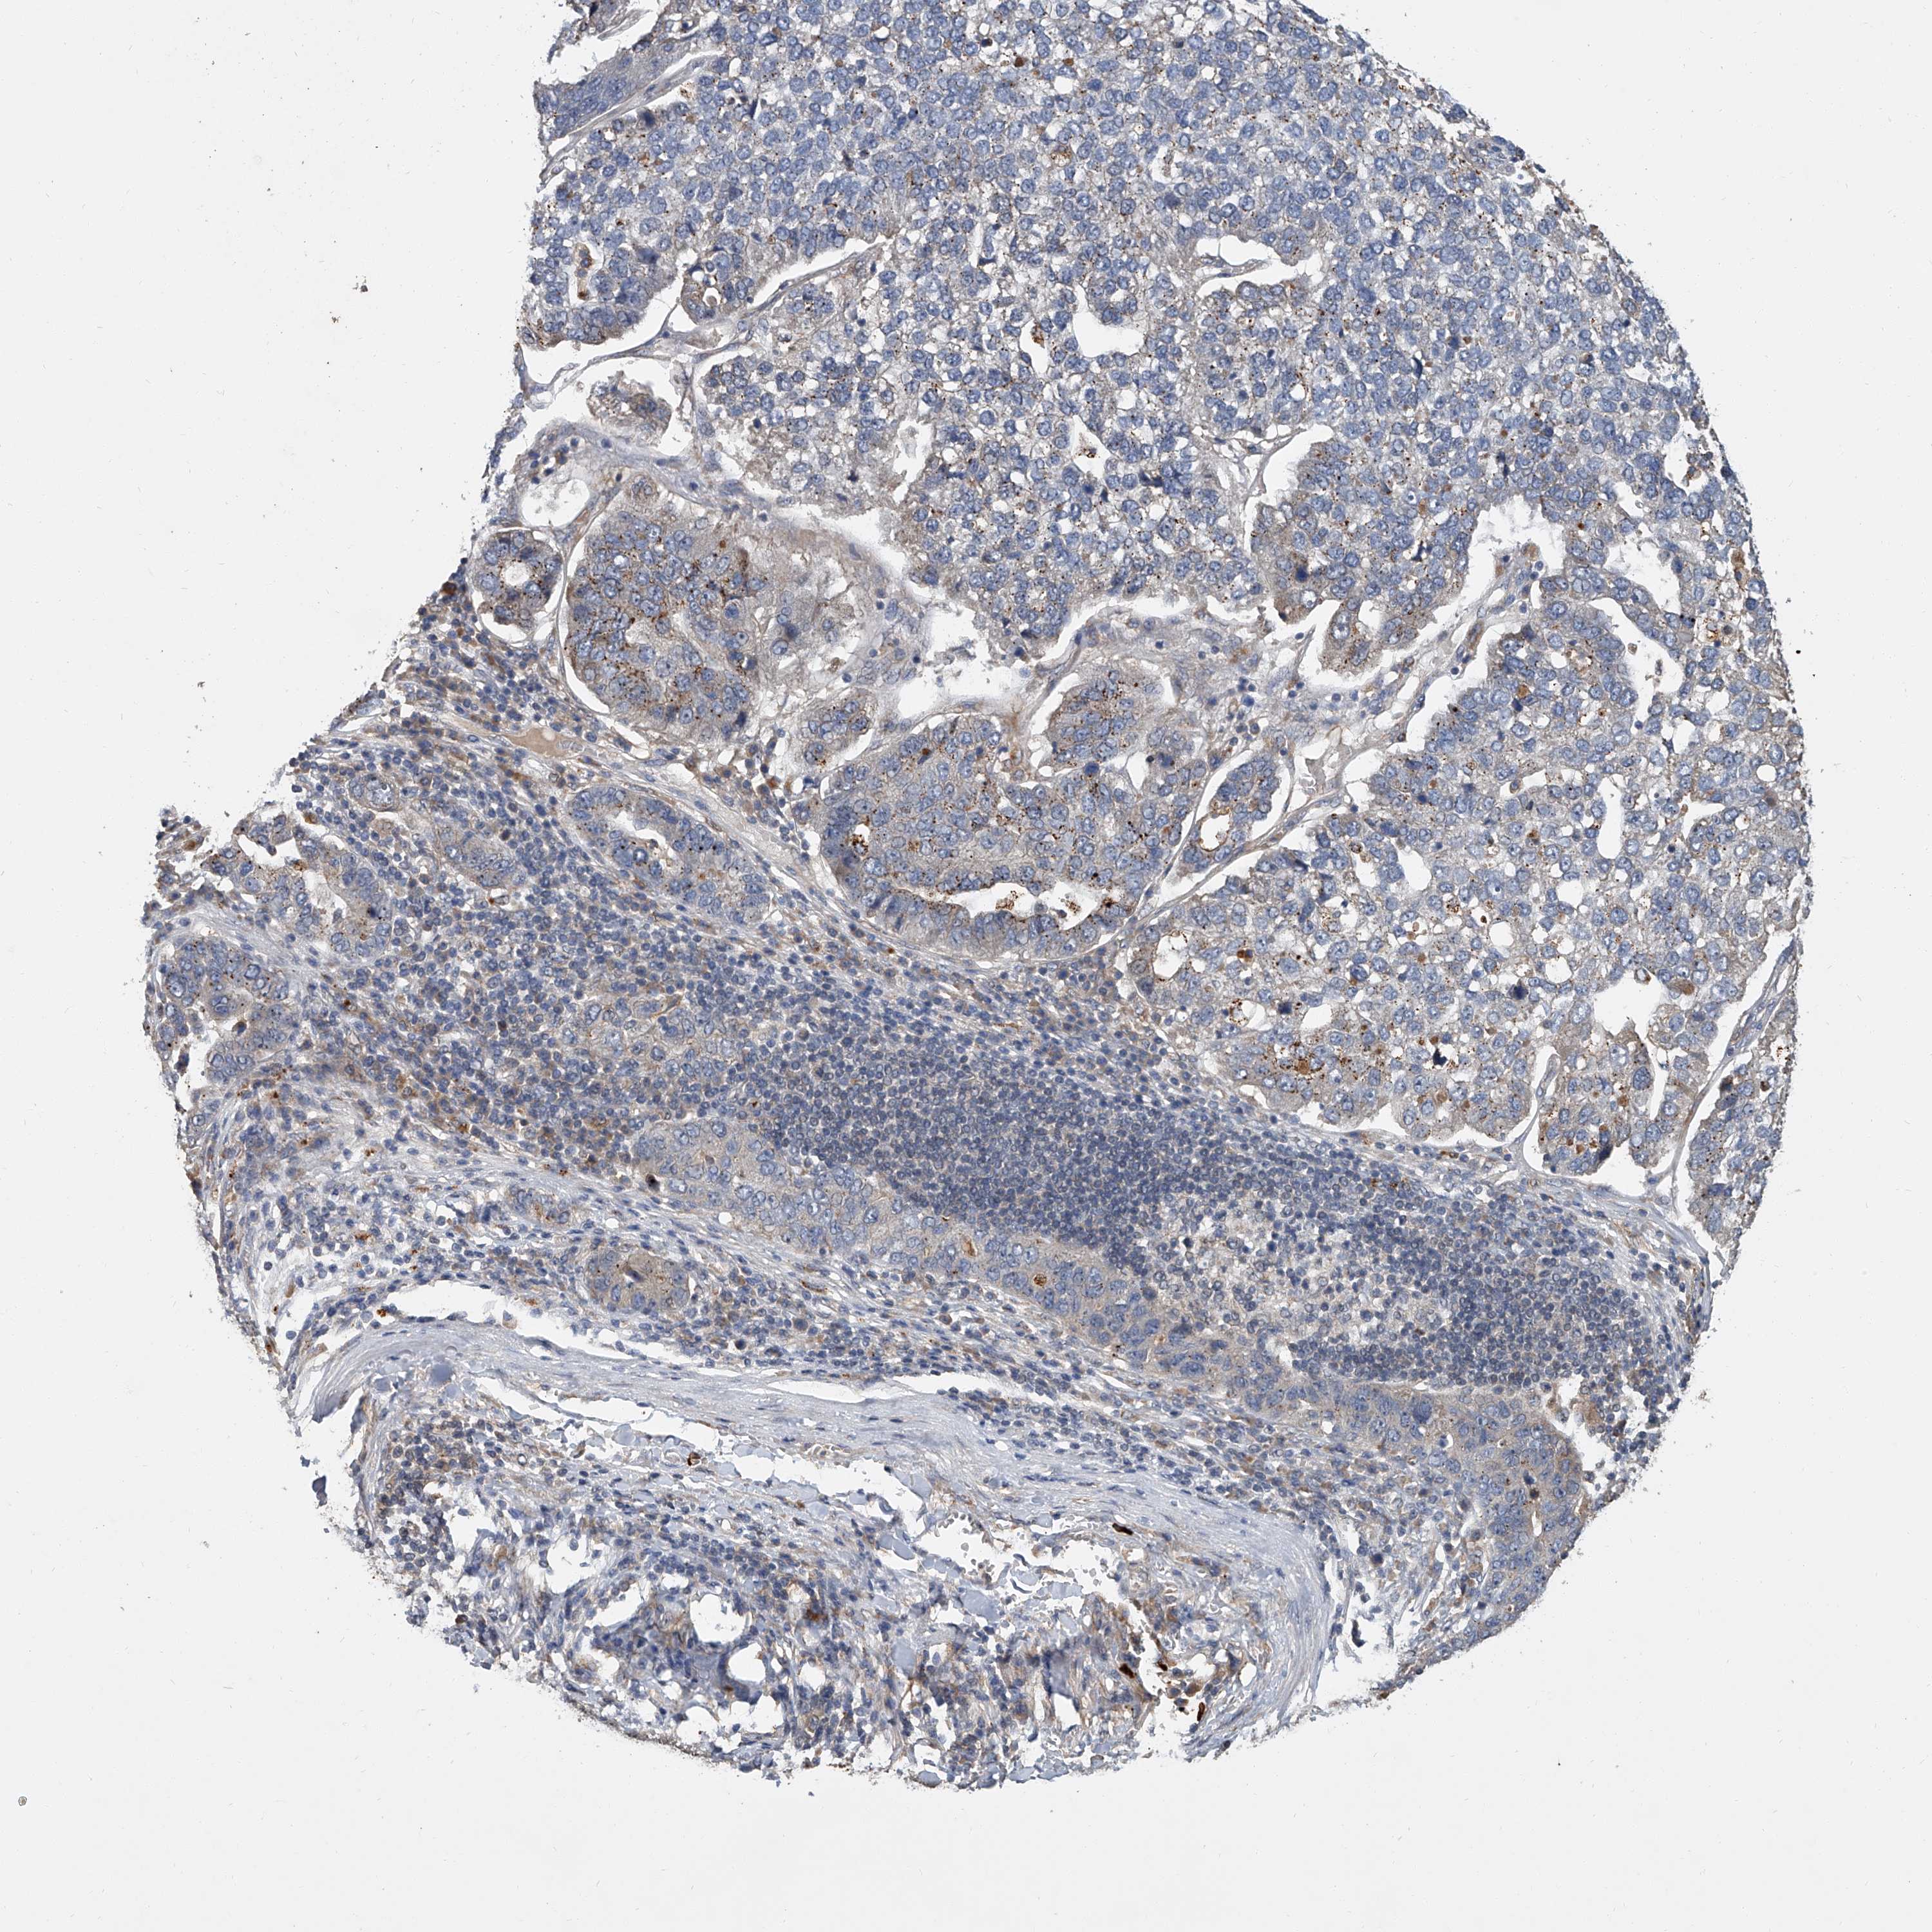

PANCREATIC CANCER - Protein expressioni

A mouse-over function shows sample information and annotation data. Click on an image to view it in a full screen mode. Samples can be filtered based on level of antibody staining by selecting one or several of the following categories: high, medium, low and not detected. The assay and annotation is described here.

Note that samples used for immunohistochemistry by the Human Protein Atlas do not correspond to samples in the TCGA dataset.

Antibody stainingi

Antibody staining in the annotated cell types in the current human tissue is reported as not detected, low, medium, or high, based on conventional immunohistochemistry profiling in selected tissues. This score is based on the combination of the staining intensity and fraction of stained cells.

Each image is clickable and will lead to virtual microscopy that enables deeper exploration of all samples and also displays staining intensity scores, fraction scores and subcellular localization as well as patient and tissue information for each sample.

Antibody HPA030636

Antibody CAB025481

Staining

High

Medium

Low

Not detected

Intensity

Strong

Moderate

Weak

Negative

Quantity

>75%

75%-25%

<25%

None

Location

Nuclear

Cytoplasmic/membranous

Cytoplasmic/membranous,nuclear

Adenocarcinoma, NOS